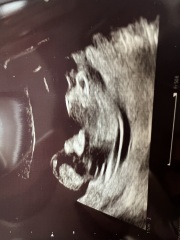

Naj08 · 04/07/2025 20:01

Is the nose bone visible in this scan? I feel like something is off with the shape and features or is that just the scan?

There’s no nose bone. As in, humans don’t have a nose bone. Look at an image of a human skull - there’s a big hole in the middle. The hard thing that feels like a bone down the middle of your nose isn’t bone, it’s cartilage.